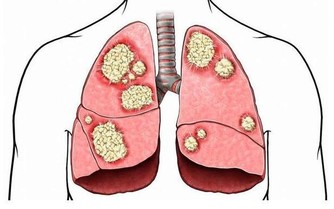

8、膽固醇越低越好?

壞膽固醇(低密度脂蛋白膽固醇,LDL)是造成動脈硬化、阻塞的罪魁禍首,好膽固醇(高密度脂蛋白膽固醇,HDL)則扮演血管清道夫角色。因此,LDL應降得愈低愈好,但HDL數值,男性需高於40mg/dL,女性則要50mg/dL以上。